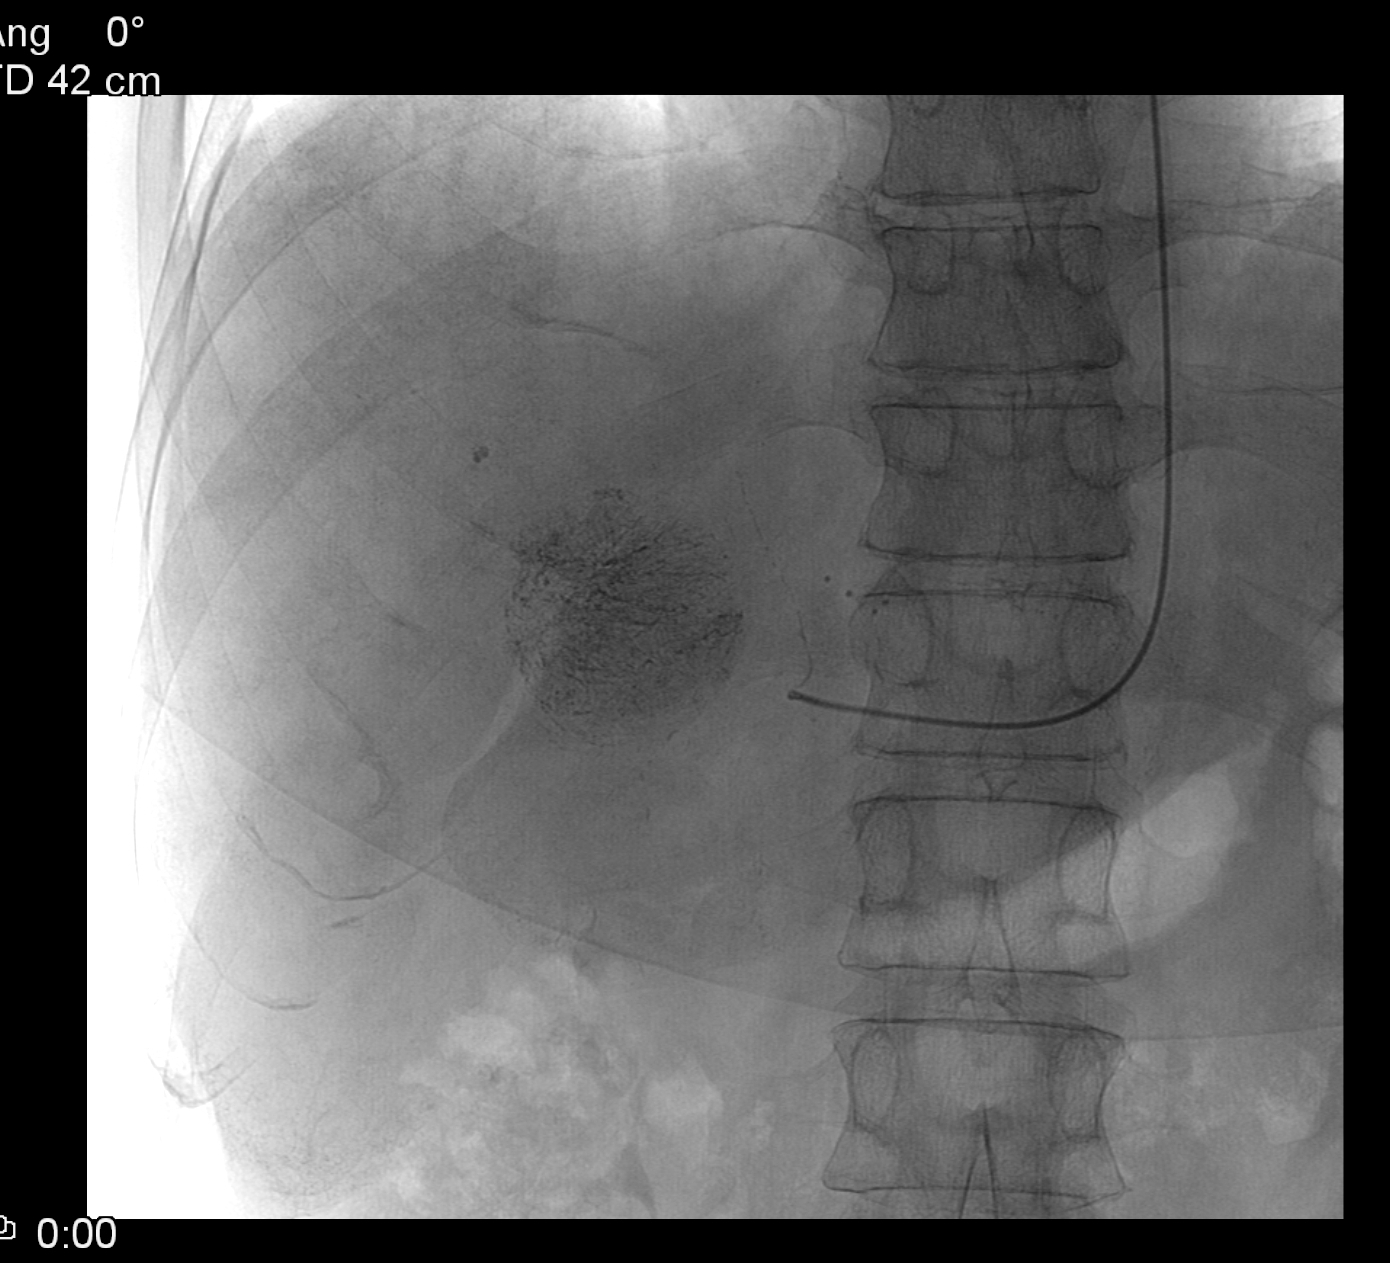

The CT-angiography and MR-angiography methods take nowadays over from the diagnostic selective catether hepatic angiographies. The catheter angiographies are performed in case of therapeutic (TAE – Figure 7, TACE, chemoperfusion) interventions and the traumatic liver injuries (selective embolisation) on these fields.

Figure 7: TAE (Transarterial Embolisation) of the liver with Lipiodol